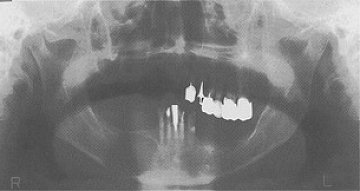

図❶

1998年9月に湯河原の歯科医師、金子 薫先生の、右下顎に嚢胞形成性の腫瘍があるという紹介状を持って来院された76歳の男性。パントモグラフのようにcystic diseaseがある(図❶)。佐々木先生が外来の担当で、この患者さんが手術のため入院され、山?が担当となった。